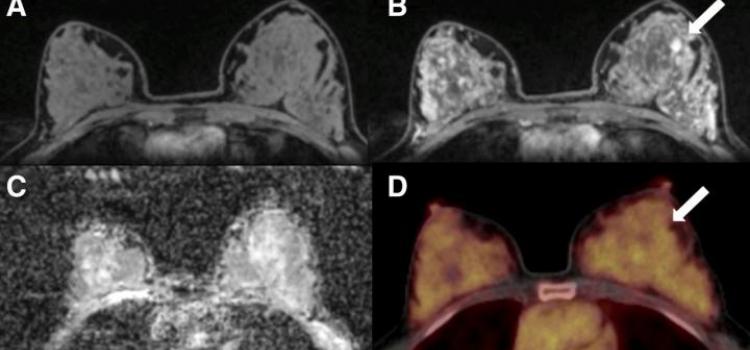

Sensitivity of axumin vs specificity of mri. A new report from a relatively small single institution study has provided additional information about the utility of 18f fluciclovine axumin pet ct scans in the detection of recurrent prostate cancer after definitive first line treatment. Axumin fluciclovine f 18 is an advanced diagnostic imaging agent or radiotracer that s used with a positron emission tomography pet computed tomography ct scan for men who have had prior treatment for prostate cancer and now have elevated prostate specific antigen psa levels. Image interpretation errors can occur with axumin pet imaging.

Conventional ct and nuclear medicine bone scans have limited sensitivity especially in patients with low psa levels less than 10 ng ml.